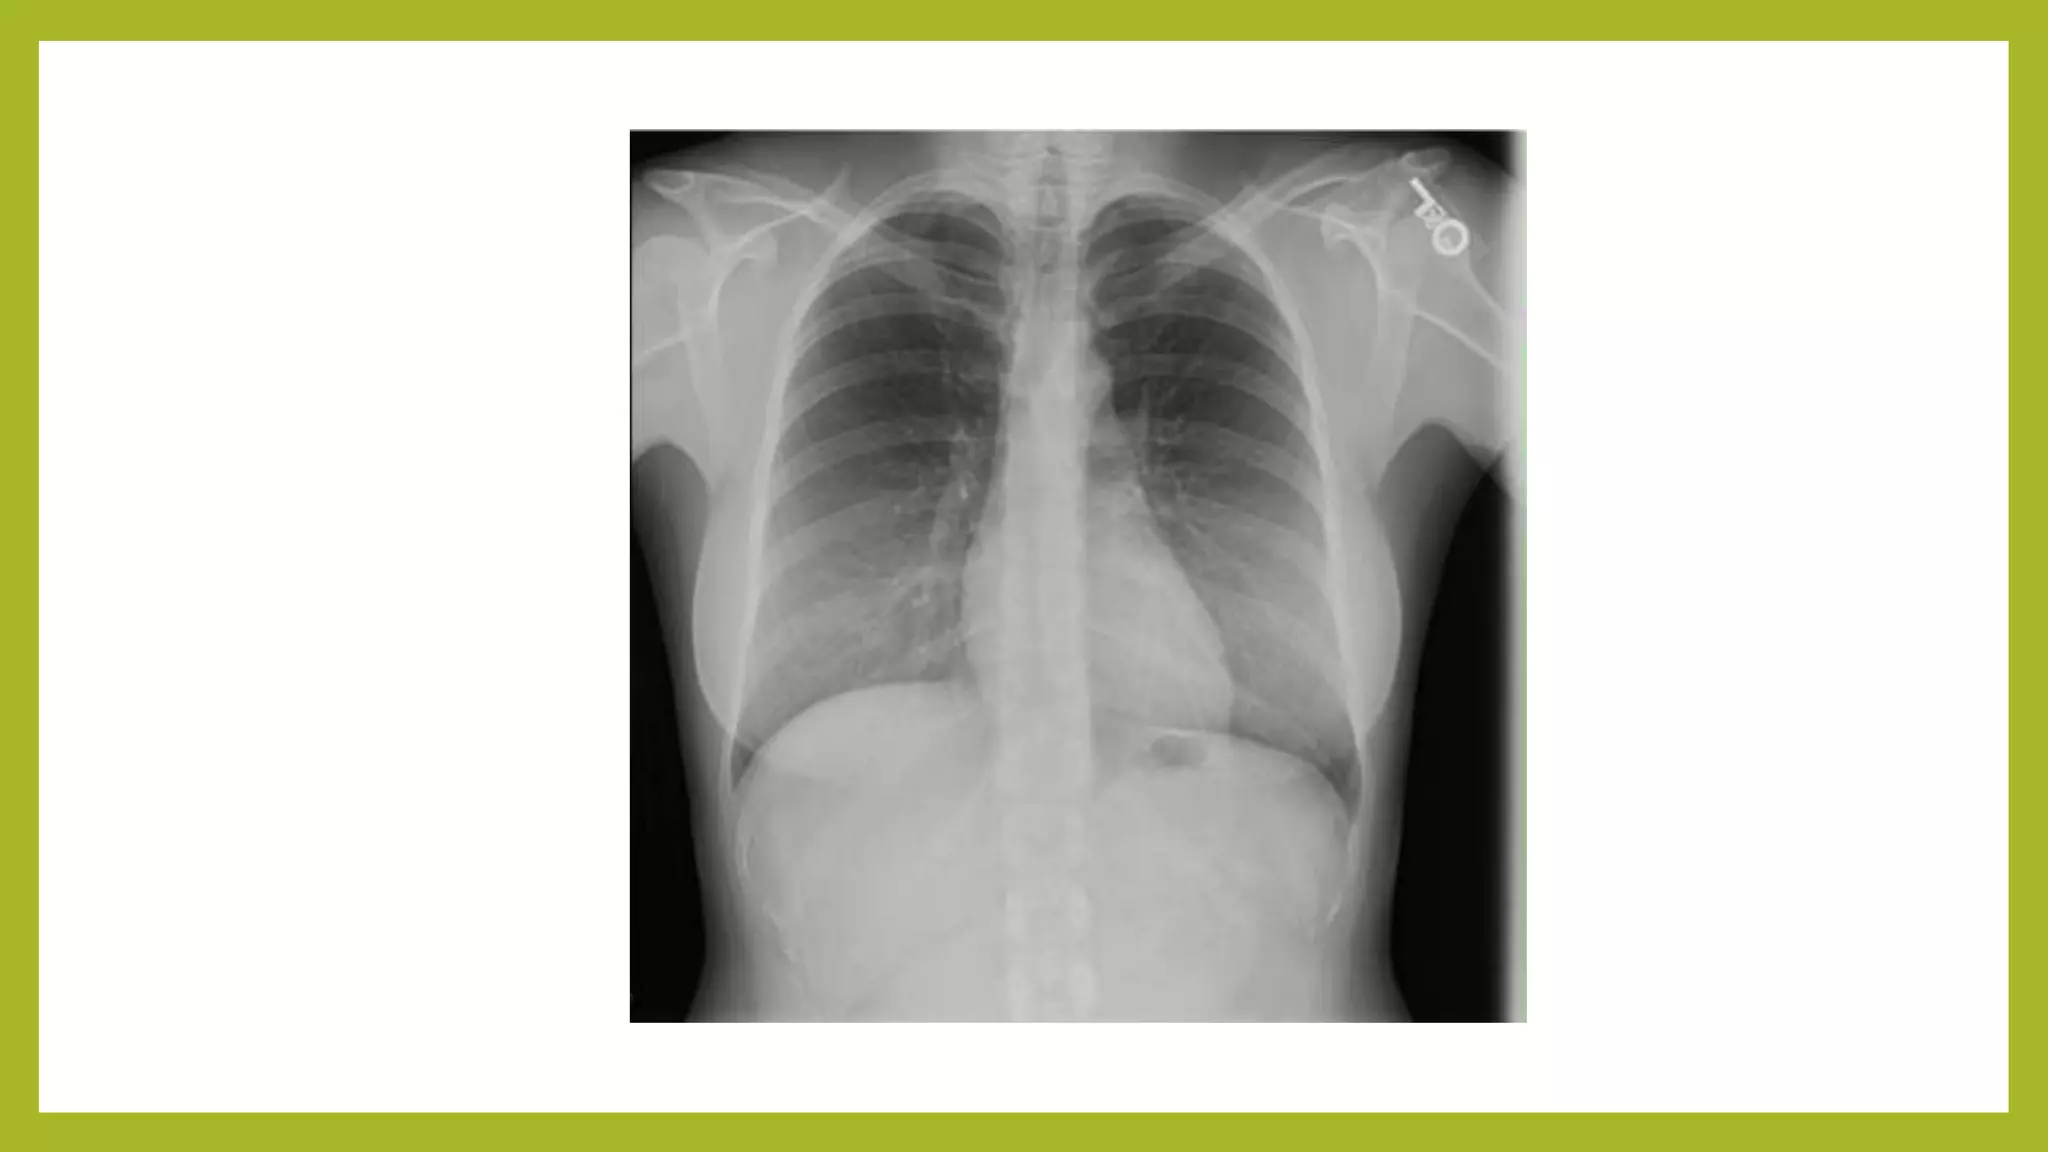

The document provides guidance on approaching and interpreting chest x-rays (CXR). It outlines steps to check the name, date and quality of the film, systematically scan the CXR looking for abnormalities, and determine if the lungs appear too white or black. Specific signs are described to help localize abnormalities, including the cardiac silhouette sign and pleural effusion signs. Examples are given of respiratory distress syndrome, tetralogy of fallot, transposition of great arteries, and total anomalous pulmonary venous return. The take home message is to summarize positive findings, compare to prior CXRs if available, and confirm findings with a radiologist.